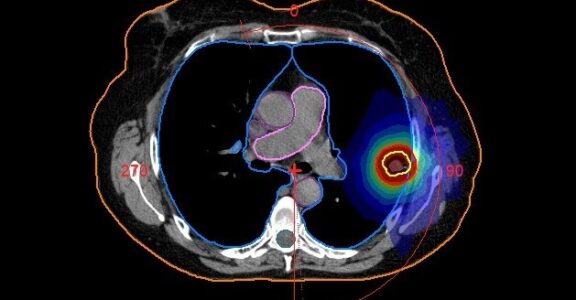

• Radiotherapy lung treatment plan

Radiotherapy treatment planning

Radiotherapy treatment planning is a process that helps ensure radiation targets the cancer as accurately as possible while protecting healthy tissue.